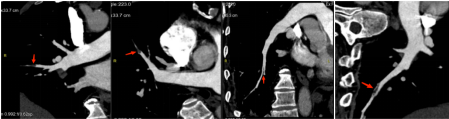

随即安排患者住院。住院后进一步完善了肺动脉CTA检查,CTPA显示:1.右肺下叶内底段肺动脉分支栓塞2.双肺炎症 3.双肺陈旧性病灶、肺气肿、肺大疱 4.纵隔内数枚小淋巴结 5.主动脉及冠状动脉钙化 6.双侧胸膜局限性增厚。

肺动脉CT血管成像:右肺下叶内底段肺动脉分支栓塞